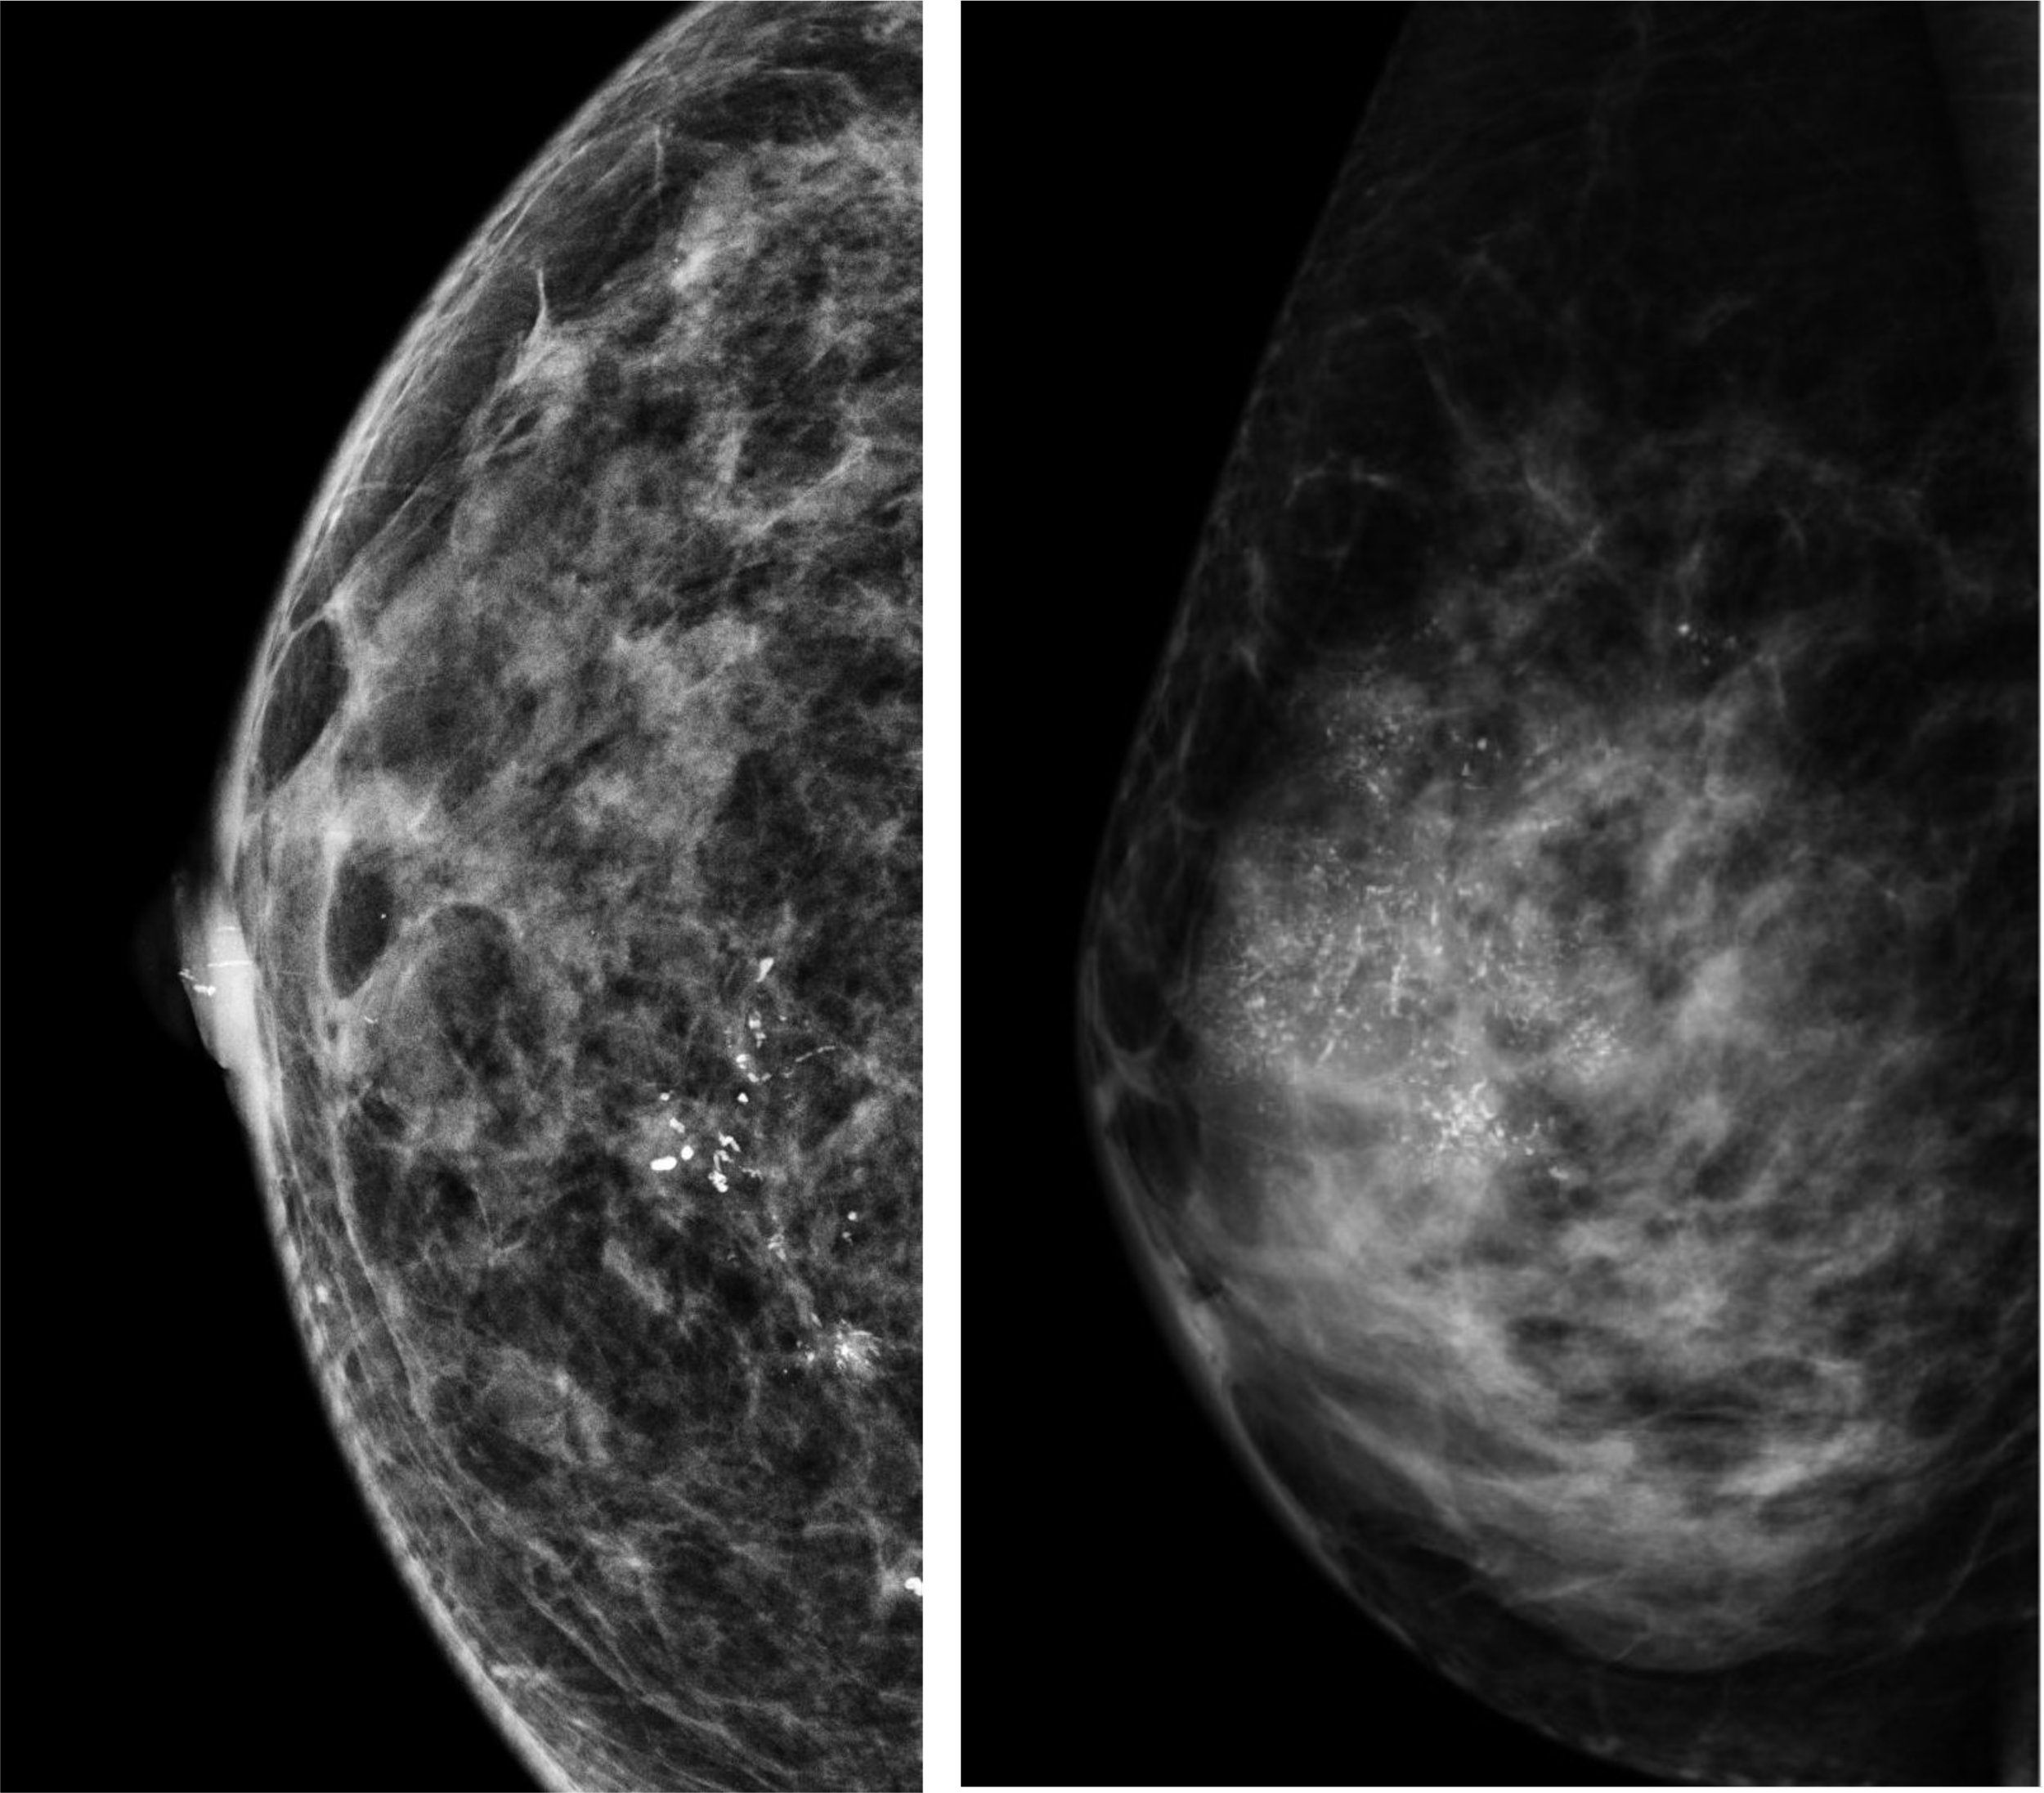

3D-Mammography

Allows for more accurate cancer detection and problem-solving (Image, courtesy of SWI).

3D mammography, aka tomosynthesis, has been shown to improve cancer detection because more images of the breast are obtained. This allows for superior visualisation of subtle abnormalities that may be obscured on 2D mammography. Similarly, overlapping breast tissues that may result in alarm from 2D mammography can be dismissed with precision. Contrary to popular belief, the radiation dose used in 3D-mammography is similar to that of 2D-mammography. Less breast compression is actually needed to obtain images in 3D-mammography.